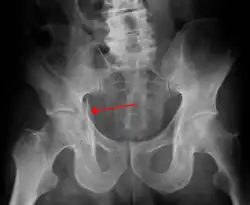

| Acetabular fracture as seen on plain X-ray |

Fractures of the acetabulum occur when the head of the femur is driven into the pelvis. This injury is caused by a blow to either the side or front of the knee and often occurs as a dashboard injury accompanied by a fracture of the femur.[1]

| Posterior wall | This is the most common variety of acetabular fracture. It typically occurs due to dashboard injury; when a person travelling in a vehicle involved in a head-on collision, the force applied over the flexed knee travels along the femur bone to the head of the femur, breaking the posterior wall of the acetabulum. The head of the femur is dislocated outside the joint. | T shape | When a transverse fracture also had a vertical fracture line, it is called a T shape fracture. Here the innominate bone is broken in such a way that all three parts of it, the ilium, the ischium and the pubis are separated from one another. This is a three part fracture. Though both columns are broken, the weight bearing dome is still attached to the main part of the ilium and hence it is not a true fracture of both columns.